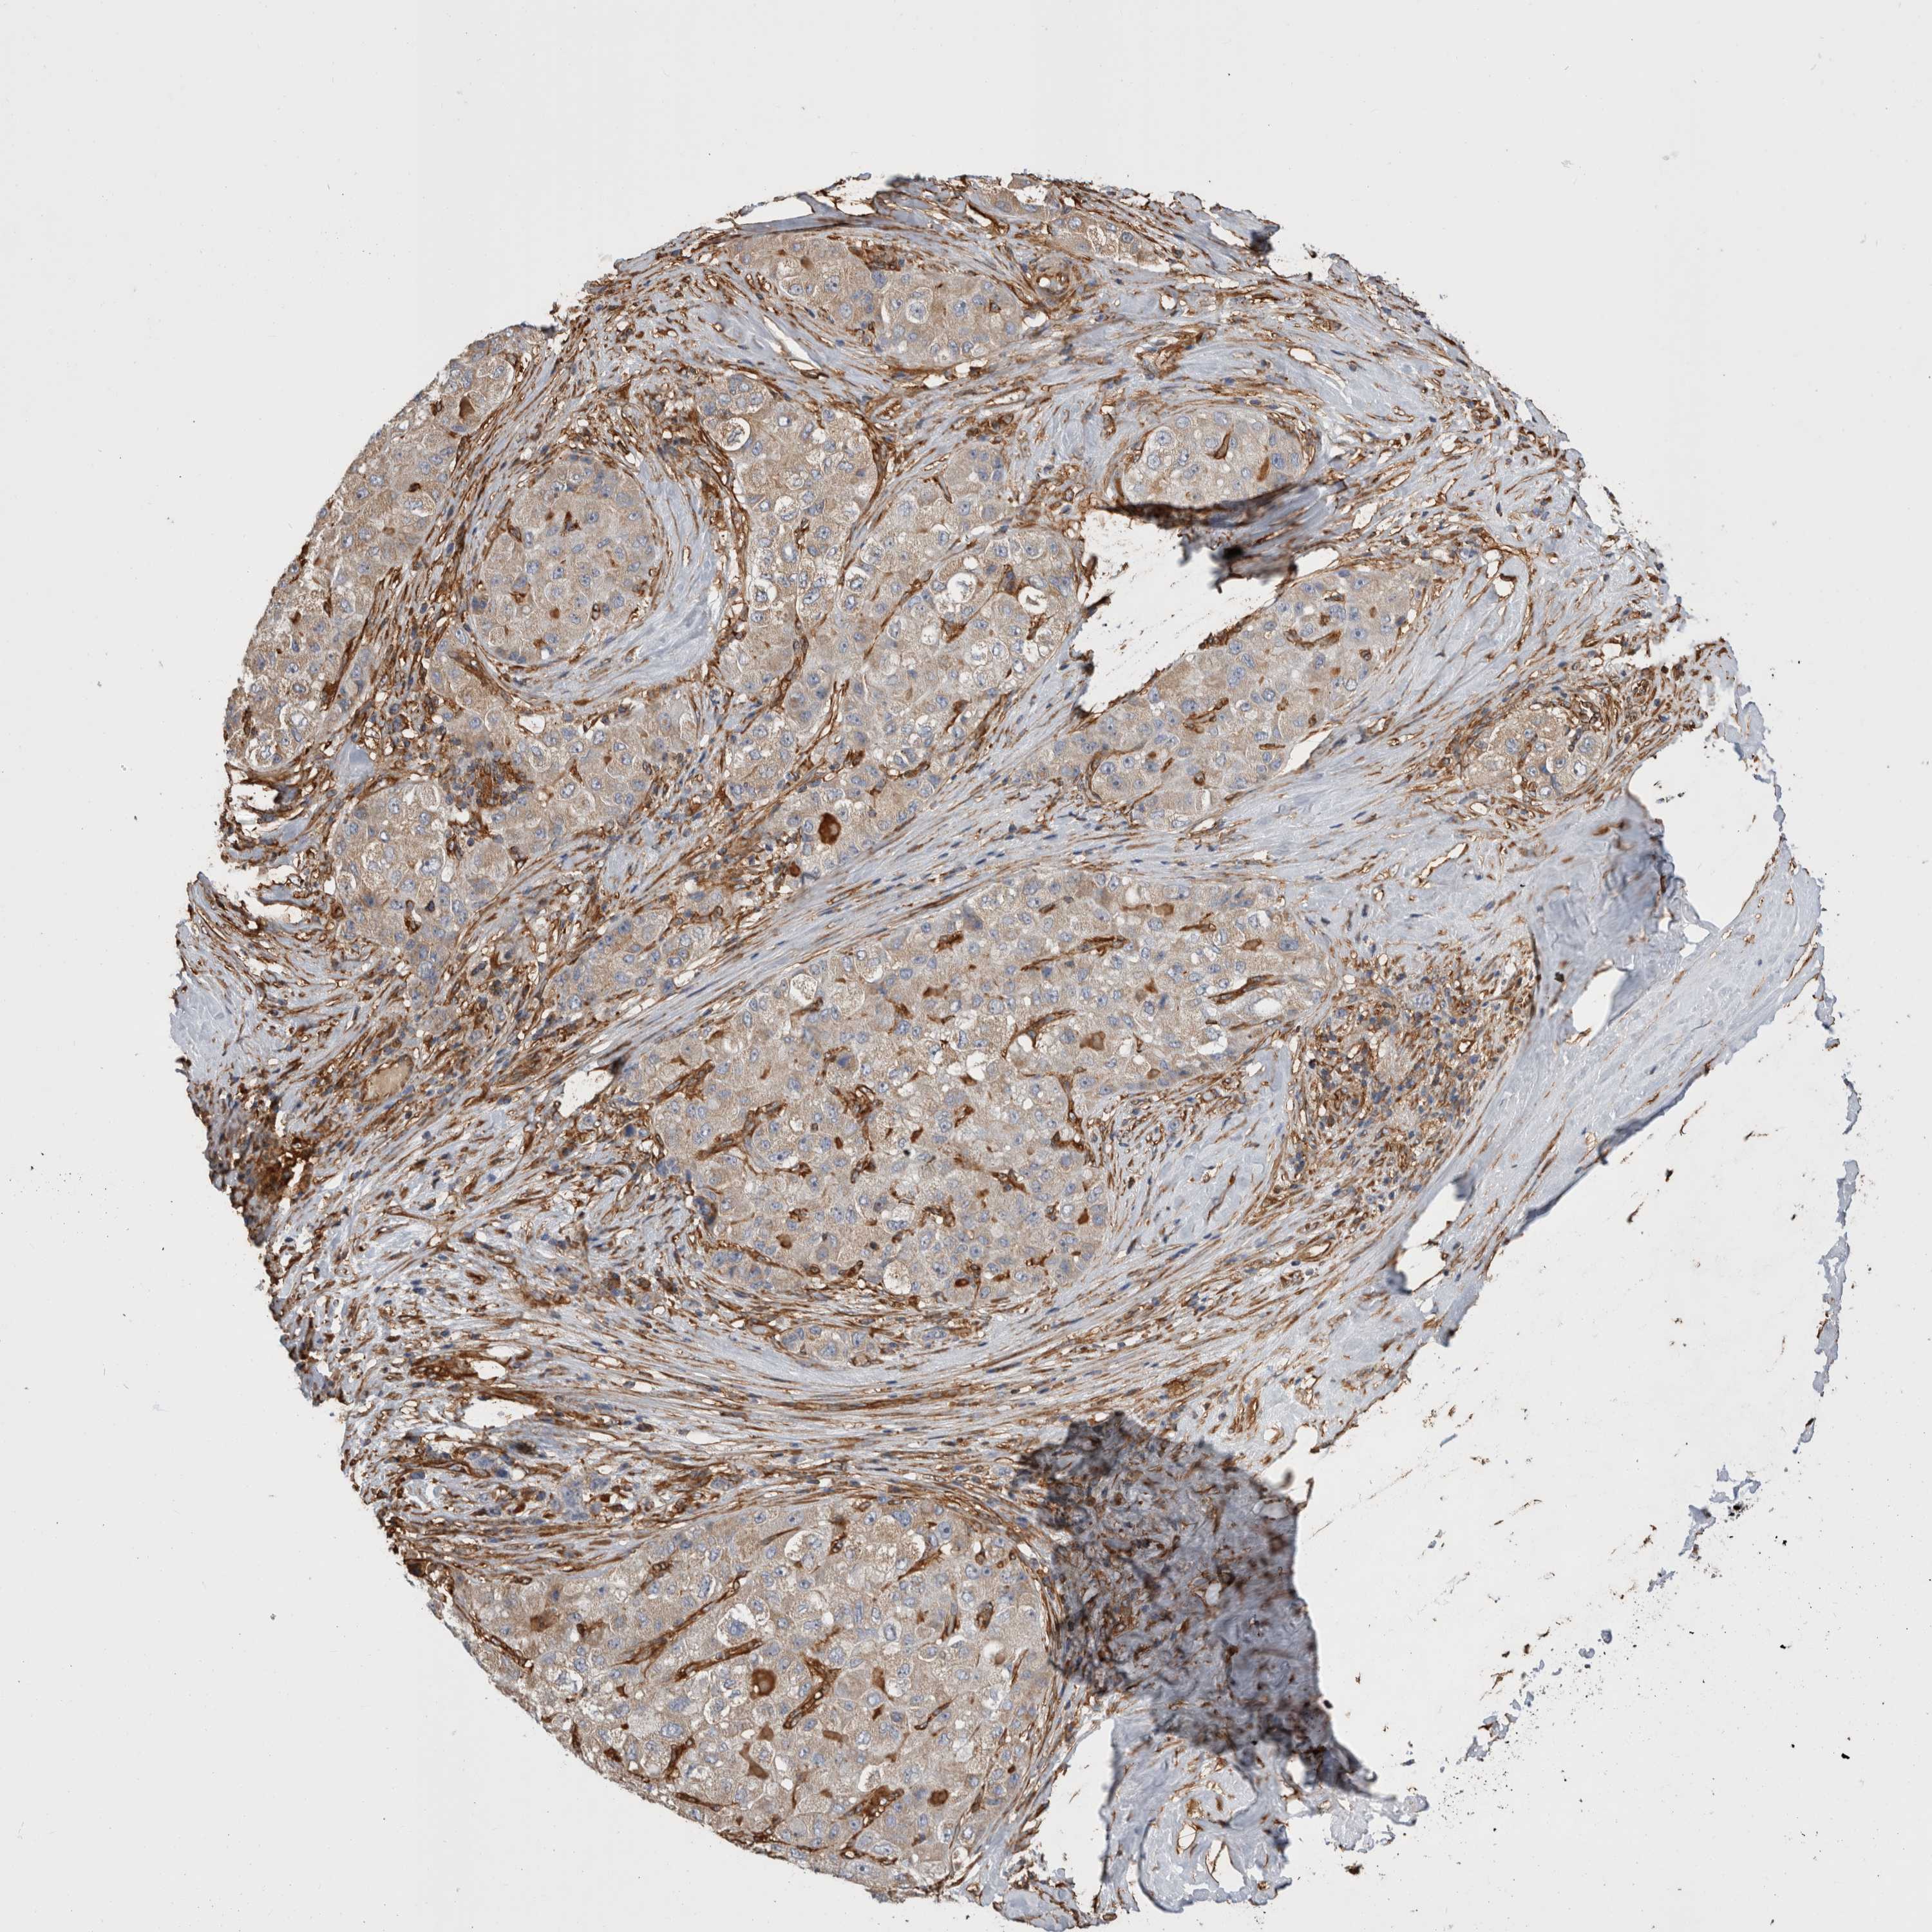

LIVER CANCER - Protein expressioni

A mouse-over function shows sample information and annotation data. Click on an image to view it in a full screen mode. Samples can be filtered based on level of antibody staining by selecting one or several of the following categories: high, medium, low and not detected. The assay and annotation is described here.

Note that samples used for immunohistochemistry by the Human Protein Atlas do not correspond to samples in the TCGA dataset.

Antibody stainingi

Antibody staining in the annotated cell types in the current human tissue is reported as not detected, low, medium, or high, based on conventional immunohistochemistry profiling in selected tissues. This score is based on the combination of the staining intensity and fraction of stained cells.

Each image is clickable and will lead to virtual microscopy that enables deeper exploration of all samples and also displays staining intensity scores, fraction scores and subcellular localization as well as patient and tissue information for each sample.

Antibody HPA026087

Staining

High

Medium

Low

Not detected

Intensity

Strong

Moderate

Weak

Negative

Quantity

>75%

75%-25%

<25%

None

Location

Nuclear

Cytoplasmic/membranous

Cytoplasmic/membranous,nuclear

Cholangiocarcinoma

Carcinoma, Hepatocellular, NOS